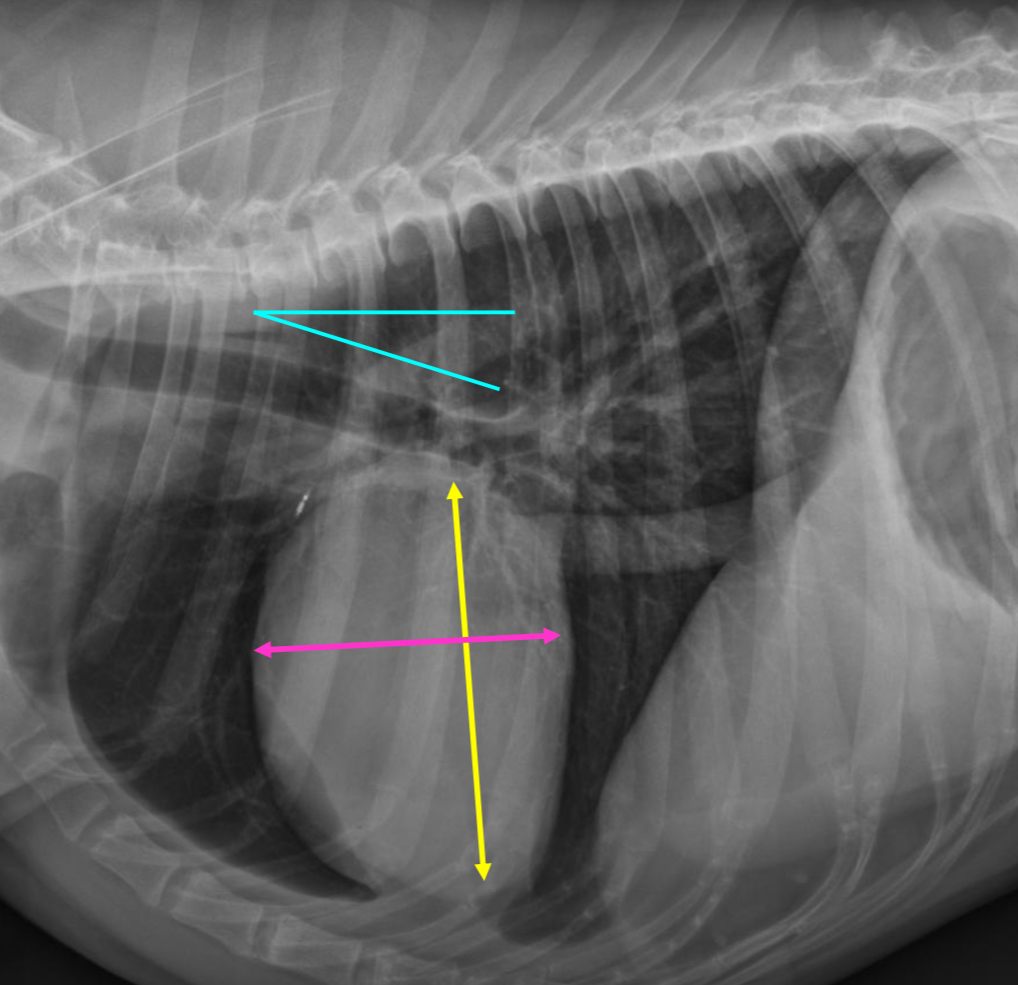

What part of the heart is enlarged

LAE

3 features of LAE on lateral

-dorsal displacement of main stem bronchi by a hunchback bump

-increased cd.dorsal cardiac border

-loss of cd.cardiac waist - straightening of cd.cardiac margin

3 features LVE on lateral

-tall heart (>2/3 DV diameter)

-dorsal displacement of trachea (almost parallel to spine)

-straightening of cd. border of heart

What part of the heart is enlarged?

LVE (technically LAE too) - prof used the same photo for both but outlined different features